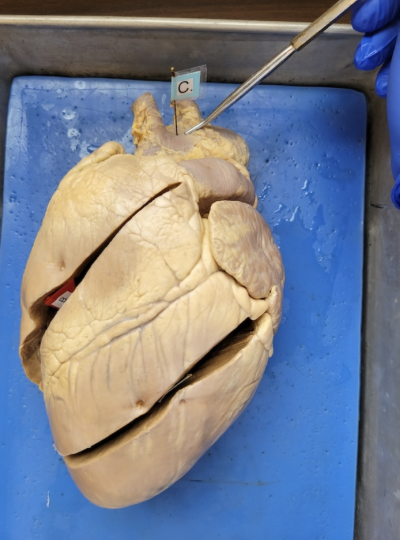

what is this

right ventricle